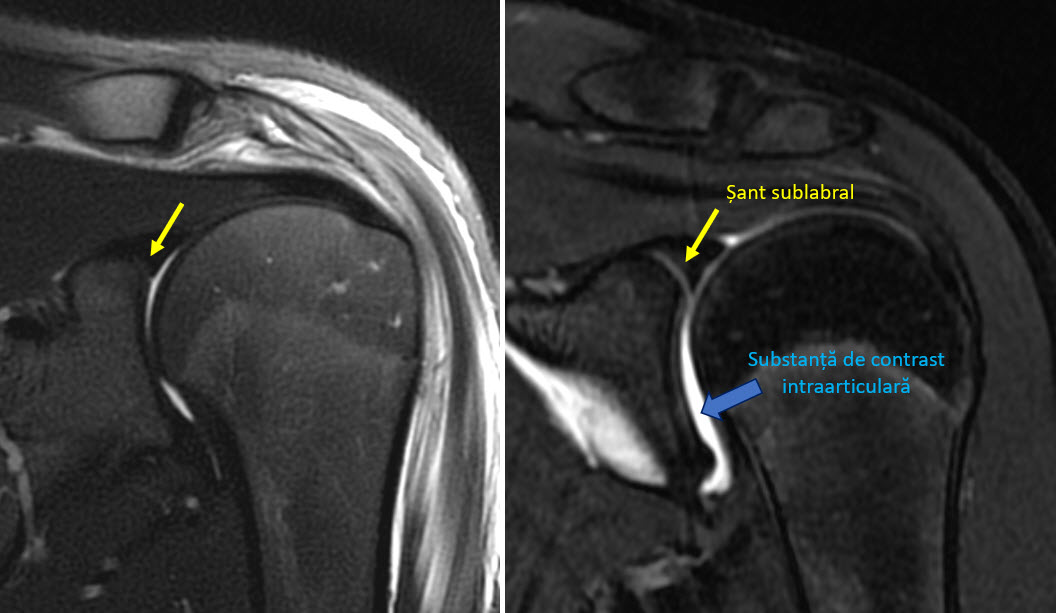

În cazuri atent selecționate poate fi necesară injectarea intraarticulară a substanței de contrast. Aceasta substanță de contrast va destinde toate recesurile articulației și va permite evidențierea leziunilor labrale, cartilaginoase sau anumite leziuni specifice cum ar fi leziunea capului lung al bicepsului de tip SLAP. Injectarea substanței de contrast se face de obicei prin abord posterior, sub ghidaj ecografic și secvențele dedicate artrografiei sunt diferite de cele dintr-o examinare prin rezonanță magnetică uzuală.

De obicei examinarea artro-rezonanță magnetică aduce informații suplimentare în cazuri selectate, după ce pacienții au avut mai întâi examinarea prin rezonanță magnetică nativă și aceasta nu a fost concludentă. Rar, atunci când mecanismul traumatismului este înalt sugestiv pentru o leziune potențial vizibilă doar pe artro-rezonanță magnetică, se efectuează artro-rezonanță magnetică fără examinarea nativă în prealabil. Chiar și în acest caz este nevoie să efectuăm câteva secvențe specifice examinării native (cel puțin un STIR/ PD cu fatsat și cel puțin o secvența T1 fără fatsat) - în caz contrar, anumite patologii acute, cum ar fi contuziile osoase sau fracturile oculte ar putea rămâne inaparente.